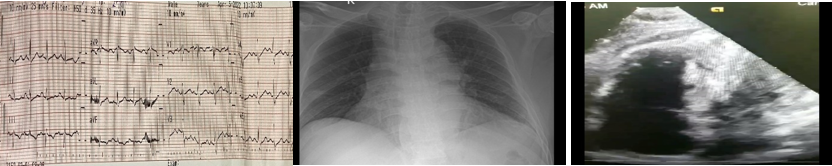

Cận lâm sàng: Bạch cầu 11.4 x103 /μL, Troponin Ths 295.7 ng/l, D-dimer: 9997 ng/ml,  ALT 254U/L và AST 165 U/L. ECG: Nhịp nhanh xoang, tần số 110 l/ ph, hình ảnh S1Q3T3. Siêu âm tim: Giãn thất phải, đường kính đáy 45 mm, dấu hiệu McConnell (+), chức năng tâm thu thất trái bình thường EF 78 %, tăng áp phổi Paps 53 mmHg. Các xét nghiệm khác trong giới hạn bình thường

ECG: Hình ảnh S1Q3T3                 X quang : Bóng tim lớn, trường phổi sáng           Siêu âm: McConnell (+)